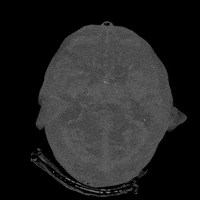

Asl Religion GIFdance image GIFtrove dragonfly by GIF IT UPheart ct GIF by Medical Imaging & Technology Alliancebrain scans tech GIF by General Electricbrain scans tech GIF by General ElectricCringe Reaction Gif GIFouter space tech GIF by General Electricvintage vhs GIF by rotomanglerouter space tech GIF by General Electric